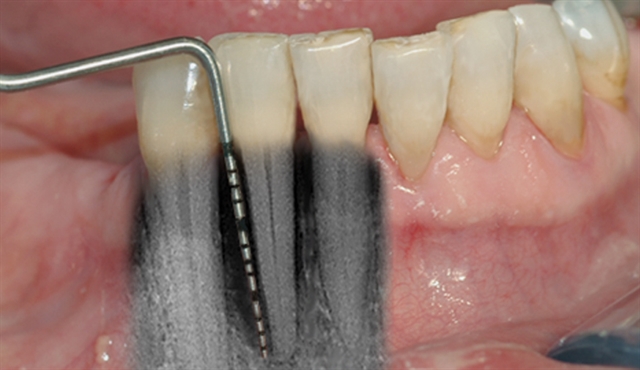

perio stor 3

Instrumentet er her lagt utenfor tannkjøttet for å vise hvor stort festetapet egentlig er.